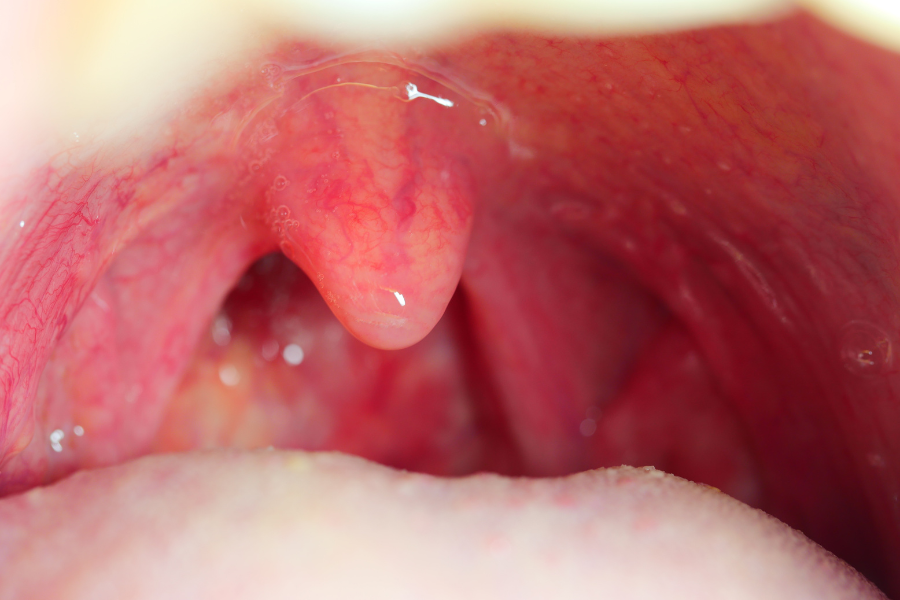

70代の口と喉はどう変わる?

70代では、身体的にも精神的にも老化が本格的に進行し始めます。それは「口」や「喉」の機能にもはっきりと現れてきます。

嚥下には、のど仏を持ち上げる筋肉(喉頭挙上筋群)や咽頭収縮筋が関わっています。70代ではこれらの筋肉も徐々に衰え、飲み込む動きが弱くなり、誤嚥(食べ物が気道に入ってしまう)のリスクが高まります。

加齢に伴い、喉の感覚が鈍くなることで、むせたり、誤嚥したりしても気づきにくくなる現象(サイレントアスピレーション)が起こりやすくなります。自覚がないまま肺に食べ物が入り込み、誤嚥性肺炎を繰り返している方も少なくありません。